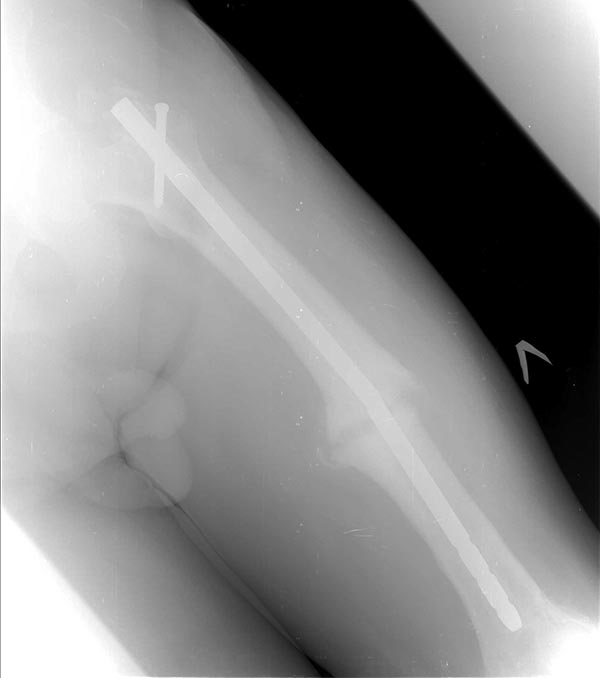

Коротко о пациенте: Возраст 60 лет, мужчина. Со слов травма в 2006 года-ДТП (сбит автомашиной) - в январе 2007 г. выполнено БИОС левого бедра , затем по неизвестным причинам в 2008 году реостеосинтез левого бедра штифтом ( снимков нет). Оперирован в одном из городов Сибири. Передвигался с тростью, с июля 2014 г. был вынужден встать на костыли в связи с усилением болей в области левого коленного сустава, левого бедра. В декабре 2014 г. боли в левом бедре усилились, появилась поталогическая подвижность.Сопутствующие заболевания:

На снимках( это снимки январь 2015г), которые выложил, определяется гипертрофический ложный сустав с/3 бедренной кости, перелом штифта на уровне перелома, штифт канюлированный.Состояние больного удовлетворительное, по анализам компенсирован.